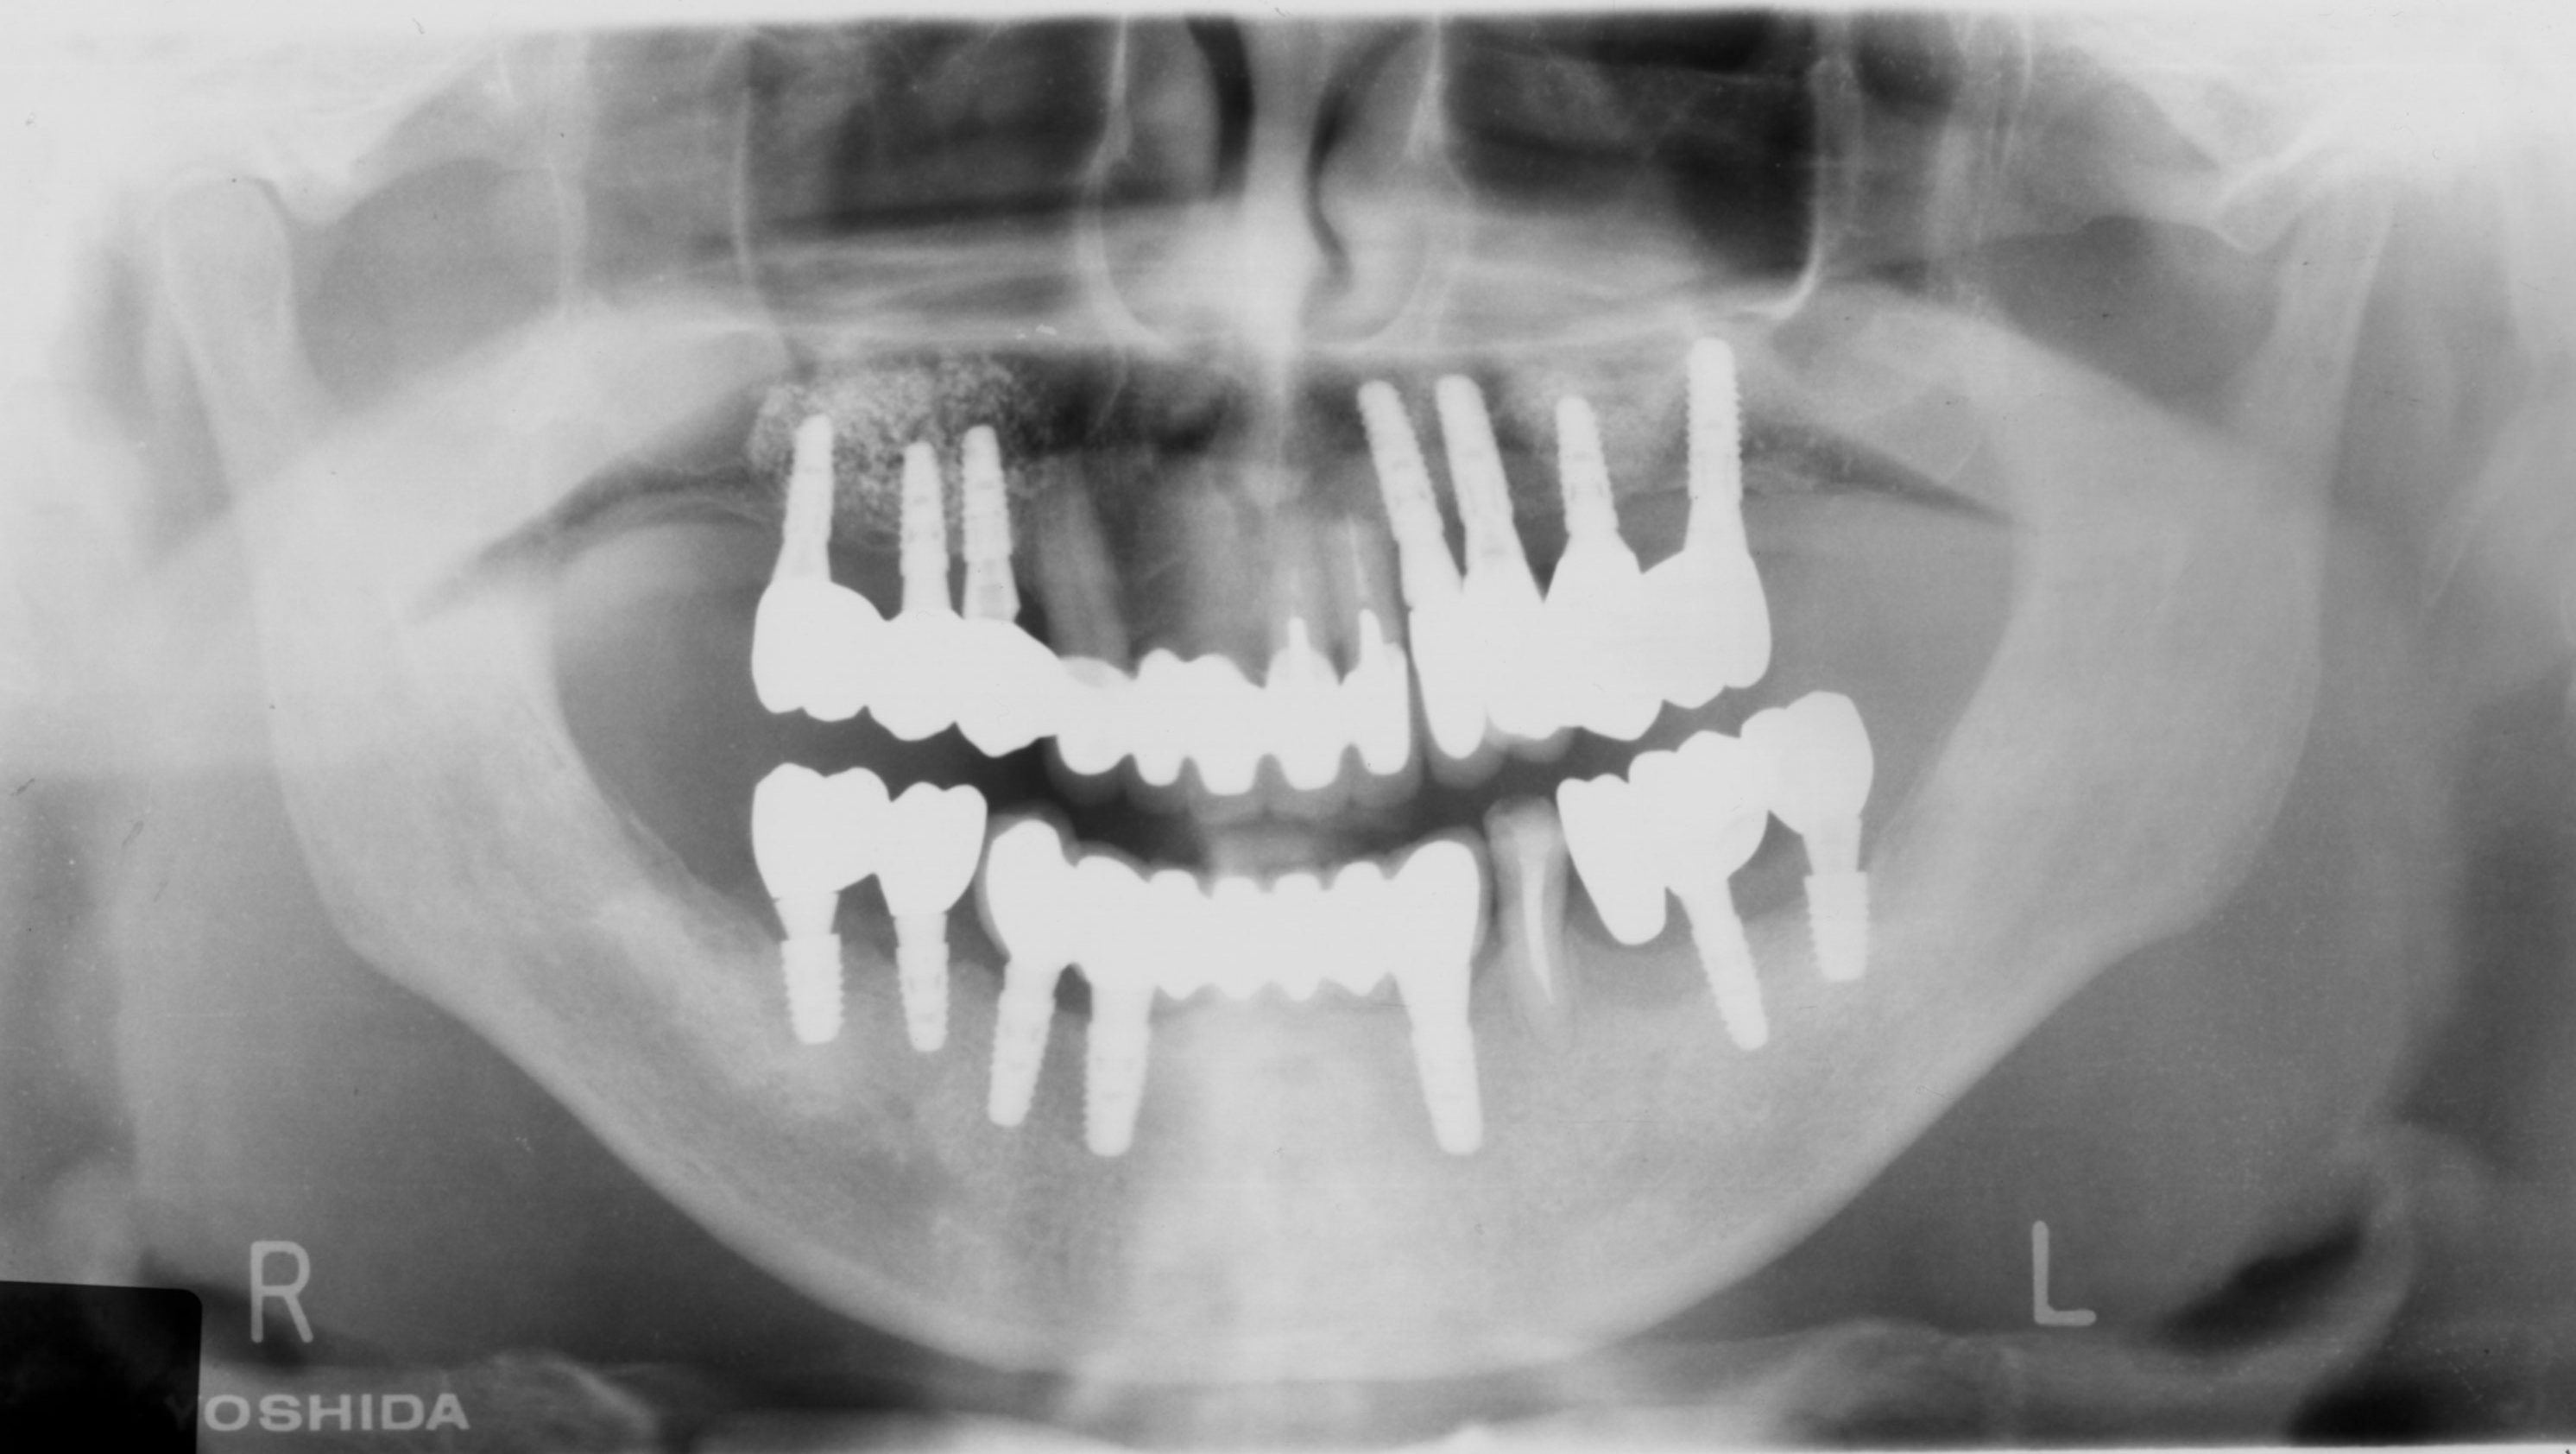

重度歯周病患者にインプラント治療(続き)

インプラント、重度歯周、サイナスリフト、ネジ山

重度歯周病患者にインプラント治療

重度歯周病

骨が足りない